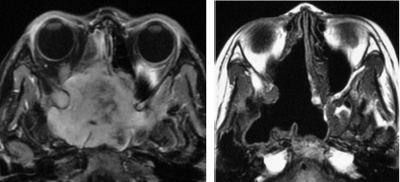

鼻咽纤维血管瘤

骨化纤维瘤

斜坡脊索瘤

图8 鼻内镜外科技术的延伸:鼻颅底、鼻眼相关精准手术